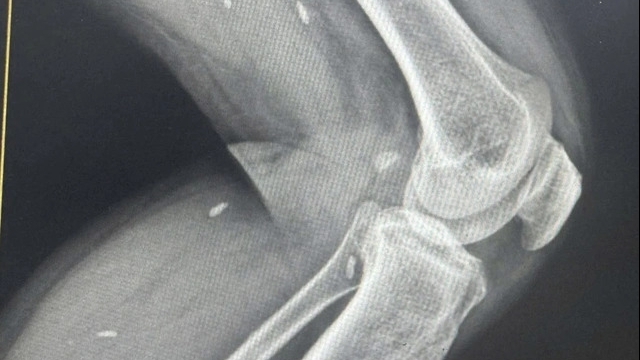

Nguồn tin từ bệnh viện cho biết, chiều 1/7, bệnh nhân Bùi Văn Tích (sinh năm 1987, trú tại huyện Lạc Sơn, Hòa Bình) là một trong hai nạn nhân trong vụ tai nạn lao động tại tòa nhà văn phòng cho thuê và kinh doanh dịch vụ thương mại (số 358 - 360 phố Nguyễn Lương Bằng, TP Hải Dương do công ty TNHH Hòa Xá làm chủ đầu tư) đã tỉnh táo, sức khỏe ổn định và tiếp tục được chăm sóc y tế chu đáo.

Công nhân Nguyễn Văn Huy (SN 1980, trú tại huyện Nam Sách) rơi xuống mặt sàn tầng 4, tử vong tại chỗ. Công nhân Bùi Văn Tích (SN 1987, trú tại huyện Lạc Sơn, tỉnh Hòa Bình) mắc lại ở tầng 8, bị thương nặng đã được đưa đi cấp cứu tại bệnh viện.